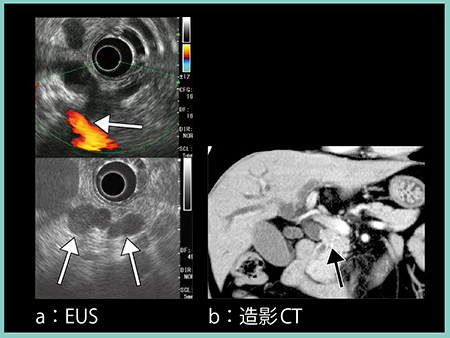

症例1は,80歳代,女性。心窩部痛を主訴に当院を受診し,超音波にて主膵管の拡張と蛇行,および低エコーの腫瘤が認められ(図1↓),膵癌を強く疑い精査となった。CTにて膵体部に造影不良域を認め(図2→),MRCPでは体部主膵管の狭窄と尾側膵管の拡張があり(図3 a←),拡散強調画像(DWI)にて陽性信号(図3 b↓)が認められたことから膵癌と診断し,外科的切除を行った。腫瘍最大径9mm,TMN分類ではT1N0M0,ステージⅠAの比較的早期の膵癌であった。

図1 症例1:早期膵癌の超音波画像